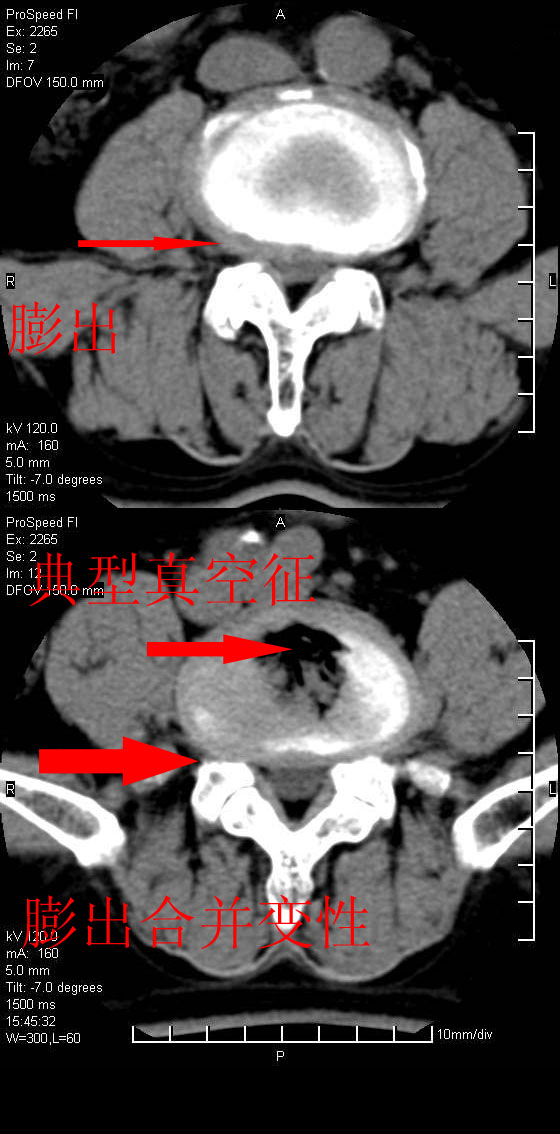

以下是引用qiushi在2007-8-22 17:26:00的发言:[br]没骨窗![br] 1、 l5~s1间盘膨出伴轻度突出(中央型)、变性。[br] 2、l4~5间盘膨出伴突出(右侧远外侧型)。[br] 3、l3~4间盘膨出。[br] 4、腰椎退行性变。[br]

以下是引用随缘的人在2007-8-22 20:56:00的发言:[br]腰椎退行性变:1。l4/5,l5/s1膨出[br] 2。l5/s1间盘退行性变 [br] 3。腰椎骨质增生

以下是引用liaizhi在2007-8-22 22:13:00的发言:[br]1,l4-5锥间盘膨出,2,l5-s1椎间盘膨出并退变(椎间盘呈真空征);3,血管瘤(椎体骨小梁稀疏粗大)?